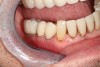

CAD/CAM dentistry is very precise. For accuracy, the preoperative, shade, bite, and upper/lower tooth scans are best taken before anesthesia and dental procedures that induce muscle fatigue (Figure 3). After infiltration anesthesia with 1 carpule of articaine hydrochloride 4% and epinephrine 1:100,000 injection, the temporary was removed. Occlusal reduction of 2.0 mm was precise and defined with an 828Y depth cutting bur to meet restorative requirements (Figure 4), and the post space was restored. Axial reduction and shoulder margination were performed with a coarse KS1 bur. After smoothing of the preparation, a 15% aluminum chloride topical gingival retraction paste was injected and compressed into the sulcus, then thoroughly rinsed with water and air-dried, before scanning of the tooth preparation and critical adjacent anatomy (Figure 5 and Figure 6).

Fig 3. Digital bite restorations are best scanned before anesthesia and restorative care.

Figure 3